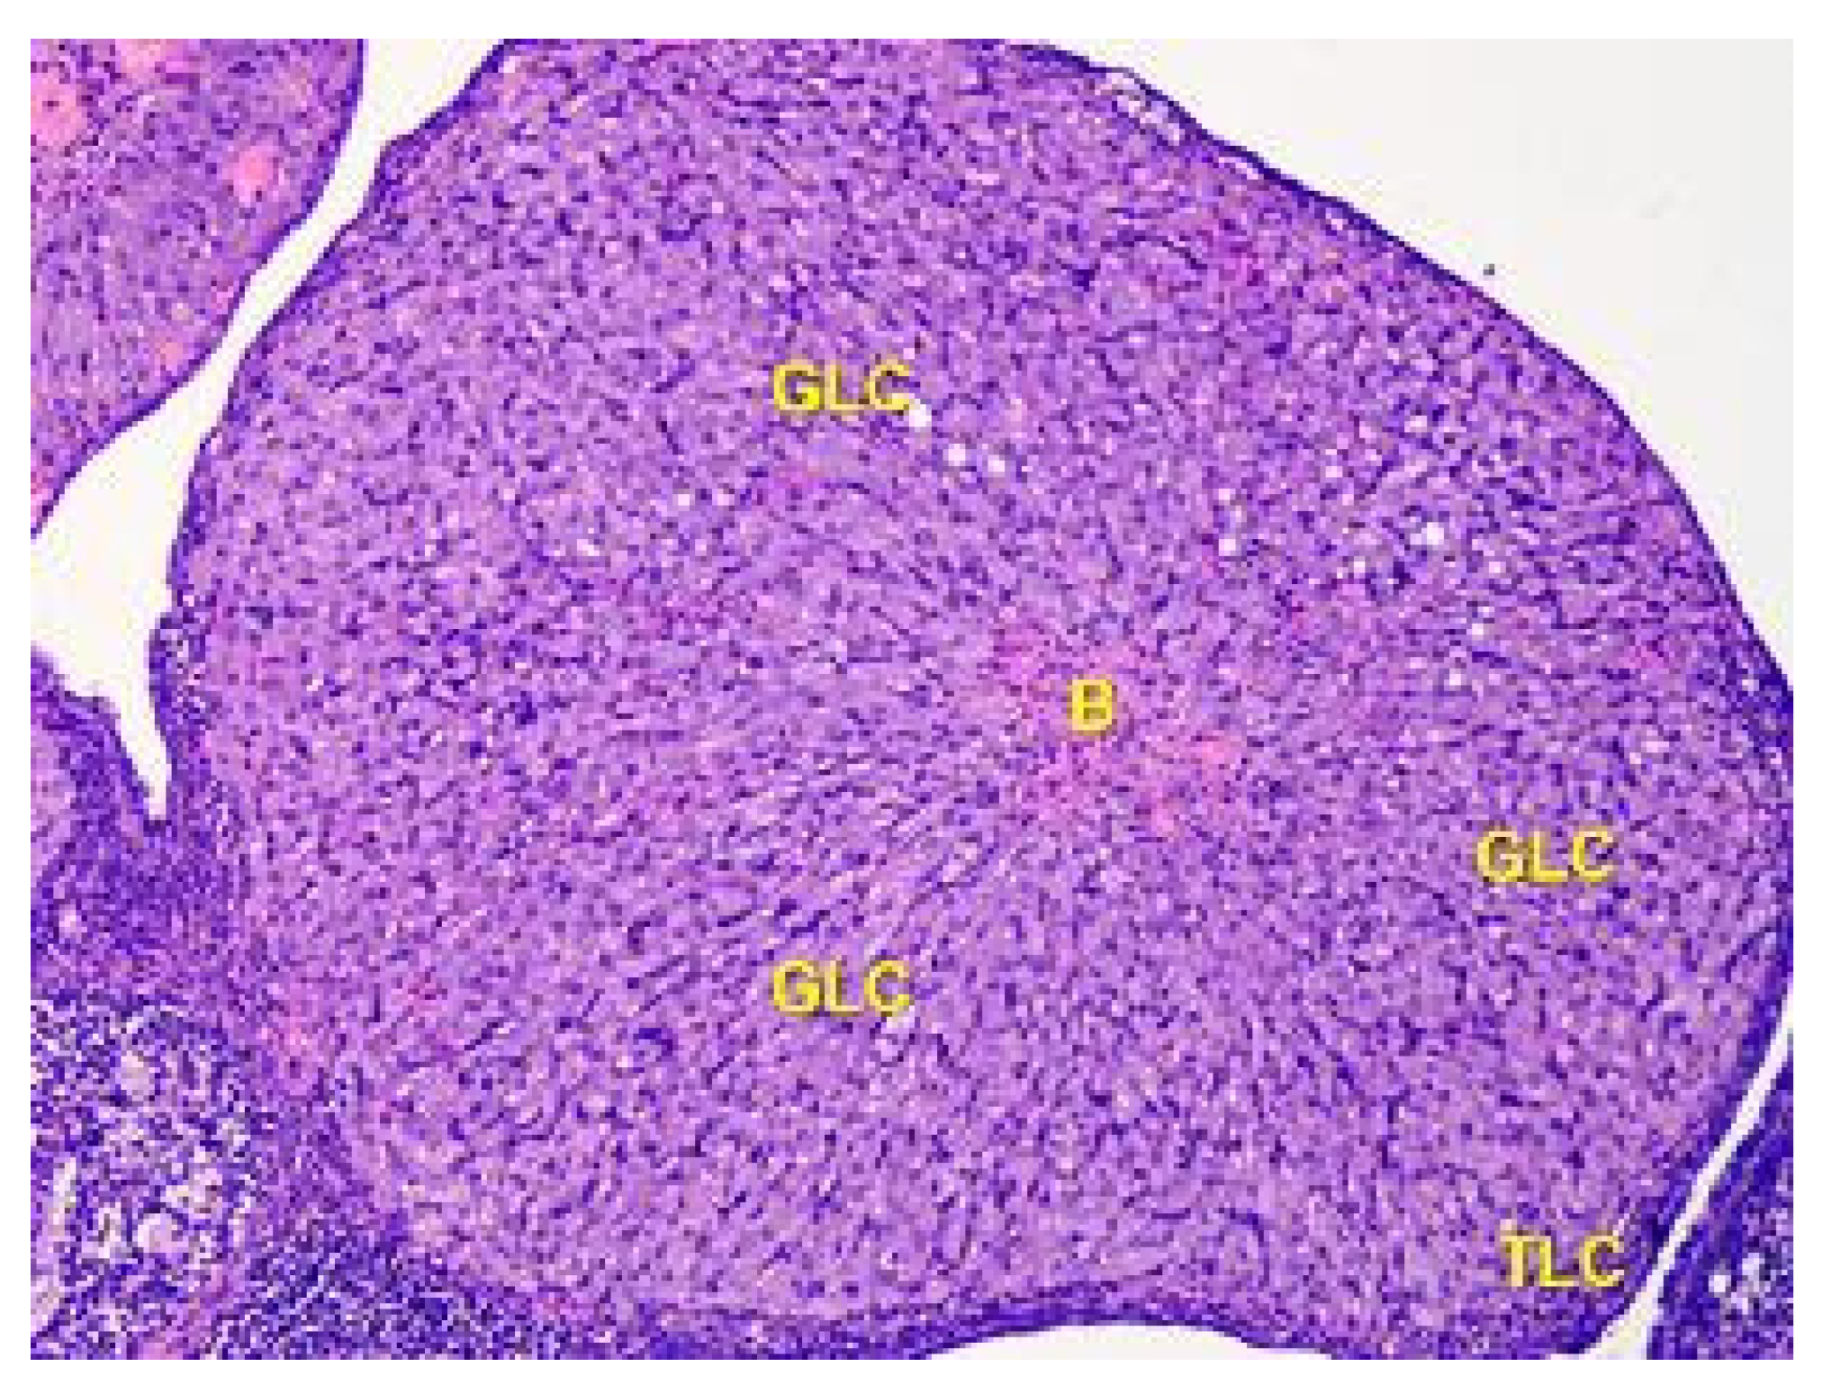

- Denefil, O.V.; Bilyk, Y.O.; Chorniy, S.V.; Fedoniuk, L.Y.; Chornii, N.V. The peculiarities of morpological changes of rats’ ovary and biochemical state under the damage with different doses of lead acetate. Wiad Lek. 2022, 75, 377–382. [Google Scholar] [CrossRef] [PubMed]